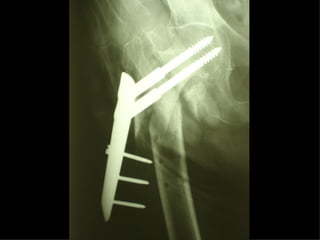

The GOTFRIED plate

La placca a compressione percutanea (PC.C.P.) di Gotfried è un mezzo di sintesi studiato per assicurare un “impattamento controllato” delle fratture pertrocanteriche grazie alle due viti telescopiche prossimali che garantiscono una ottima stabilità rotazionale

Con la placca di Gotfried non si è mai riscontrato un danno iatrogeno del muro laterale e nessun collasso della frattura.Ciò è dovuto al fatto che i fori per l’applicazione delle due viti prossimali sono di piccolo diametro (9 mm) rispetto ai 16-32 mm necessari per introdurre la vite cefalica di un chiodo endomidollare o di una vite-placca a compressione.

La placca PC.C.P. viene inoltre applicata per via percutanea attraverso due piccole incisioni ottenendo in tal modo un minimo trauma chirurgico ed una  perdita di sangue estremamente ridotta in pazienti che per l’età  sono già in condizioni  critiche

Dal Gennaio 2005 ad Agosto 2006 110  placche di Gotfried Età media  : 78 anni (range 29-94) Tempo chirurgico: 30 minuti (range 12-45) IMMEDIATA CONCESSIONE DEL CARICO